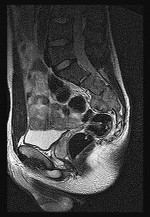

Figures 6a through 6d are the radiographs and T1-weighted sagittal and fat-saturated axial MR images of an otherwise healthy 56-year-old man who has anterior knee pain and intermittent swelling after sustaining a noncontact twisting injury. Low-power and high-power hematoxylin and eosin stained histologic specimens are shown in Figures 6e and 6f. Based on the history, radiographs, CT scan, MR imaging, and histologic findings, what is the most likely diagnosis?

The lesion in the posterior intercondylar knee notch is a benign synovial hemangioma. Intralesional calcifications, classically associated with hemangiomas, are frequently not identified on plain radiographs. The MR imaging reveals a hypervascular lesion with multiple filling defects, with hyperintensity on T2-weighted images and low-to-intermediate signal intensity on T1-weighted images. Histologically, vascular lakes within fine capillaries with a synovium on the surface of the lesion are characteristic of this condition. Many patients with synovial hemangioma have pain, swelling, stiffness, or mechanical symptoms. The correlation of symptoms with the hemangioma for this patient is unclear because there was recent trauma and a concurrent meniscus tear. Simultaneous treatment of both potential sources of pain is typically recommended. As with PVNS, the disease can be localized or diffuse. Surgical excision, either open or arthroscopic, is the recommended treatment. PVNS is the most common intra-articular tumor, but hypointensity in either the diffuse or localized type is characteristic in both T1- and T2-weighted images. Synovial sarcoma, although often found close to a joint, is not characteristically found within a joint.